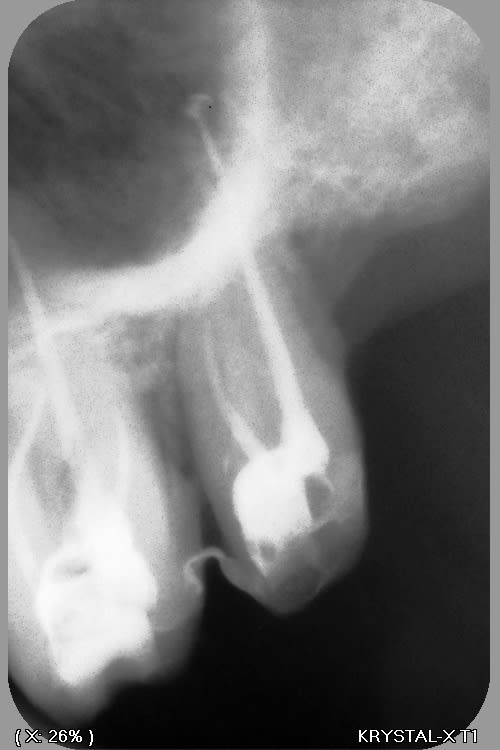

la suite

--